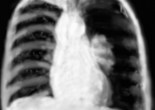

L’épanchement pleural ou pleurésie, est l’accumulation pathologique de liquide dans la cavité pleurale, autour des poumons. Celle-ci est virtuelle à l’état physiologique, ne comportant à peine que quelques gouttes de … Lire la suite

En urgence seuls les épanchements de constitution rapide sont utiles directement. Les petits épanchements pleuraux en émoussement de cul-de-sac costo-diaphragmatique sont intéressants mais ne permettent pas de conclure, sauf si … Lire la suite